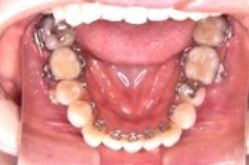

* 歯の裏側に付ける為、装置が見えない

* 歯みがきが難しい

* 治療当初、舌への違和感がある

* 1回の治療時間が表に比べて長い

大人の方で、仕事の都合でどうしても表側につけられない患者さん向けの方法です。

メリット

デメリット

* サ行・タ行の発音が治療当初不明瞭

(2~3ヶ月で慣れてきます)